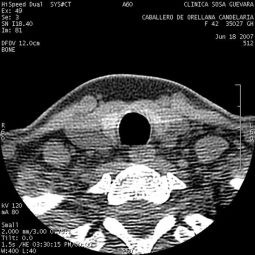

Clínica de Radiología y Ultrasonografía Sosa - Guevara

TAC de senos

Clinicas > Radiologia

VER GALERÍA